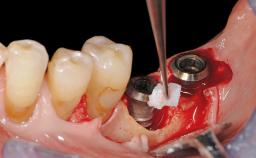

Late Presentation of Peri-Implant Mucositis Requiring Soft-Tissue Augmentation and Esthetic Crown Lengthening at Implant Site 11

Biological or technical complications around implant-supported prostheses place a significant burden on patients as well as the surgical and restorative team. Inflammation of the peri-implant soft tissues is often the first sign that something has gone awry. While there is never a good time for a complication, late presentation of inflammation in the soft tissues around a long-standing prosthesis triggers a period of research and review of the case in order to ascertain the treatment history and its possible contribution to the etiology of the situation. This becomes more complicated in situations where a patient has not received regular maintenance and clinical/radiographical examinations due to personal, financial, or professional reasons. When the complication occurs in the esthetic zone, the complexity of the situation expands exponentially, as the only acceptable outcome in the patient’s eyes will be the maintenance of the esthetics of the prosthesis.